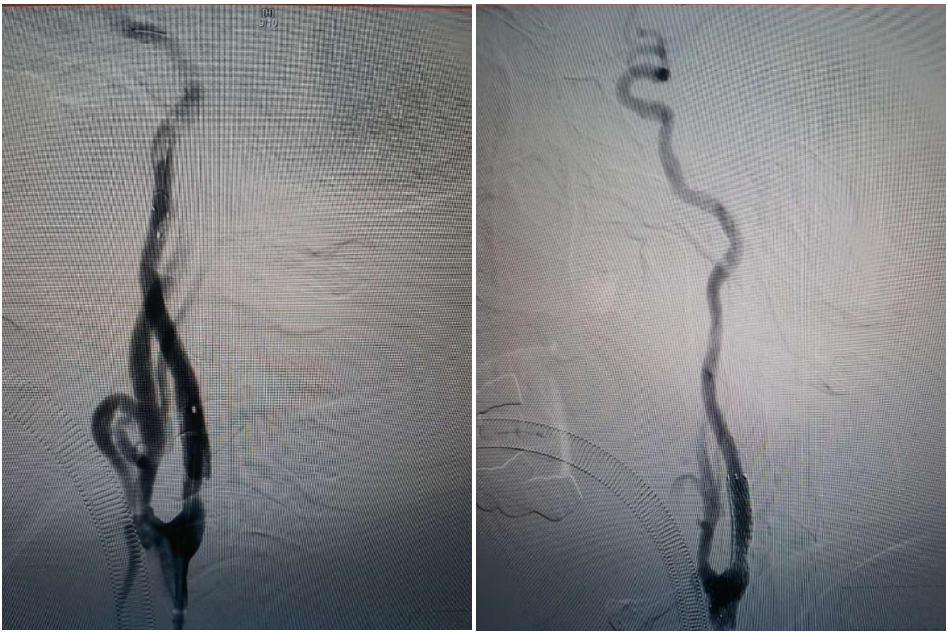

A microguidewire and microcatheter were carefully advanced through the occluded origin of the right ICA. Contrast injection through the microcatheter confirmed its position in the true lumen of the ICA. The microcatheter was exchanged for a long guidewire and withdrawn. A 2.5 mm balloon was used for pre-dilation at the occluded segment of the right ICA origin, followed by advancement of an 8F guiding catheter. A Zenith Aspiration Catheter was introduced coaxially and advanced along the ICA. Aspiration yielded a large amount of thrombus.

Post-aspiration angiography demonstrated good visualization of the right MCA and ACA.